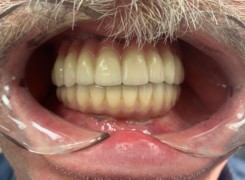

Pan Ryszard trafił do Naszego Gabinetu z jasno sprecyzowanym oczekiwaniem. Miał 84 lata i chciał odzyskać możliwość swobodnego spożywania posiłków oraz poprawienia sobie komfortu życia a także prosił aby przywrócić mu piękny uśmiech jakim cieszył się przed laty. Już na początku pierwszej rozmowy zastrzegł, że interesuje go wyłączenie rozwiązanie uzupełnieniem protetycznym stałym. Nie miał zamiaru użytkować żadnych protez ruchomych. Mając na uwadze powyższe wykonaliśmy Panu Ryszardowi zdjęcie pantomograficzne oraz badanie tomograficzne szczęki i żuchwy na postawie których zapanowywaliśmy Pacjentowi optymalne rozwiązanie – stałe uzupełnienie protetyczne w postaci 28 koron cyrkonowych zamontowanych do dwóch belek cyrkonowych które będą przymocowane do 16 implantów w konfiguracji 8 wszczepów w szczęcie 8 w żuchwie. Po omówieniu powyższego planu przystąpiliśmy do Wspólnej pracy której efekty w poszczególnych etapach prezentujemy poniżej.